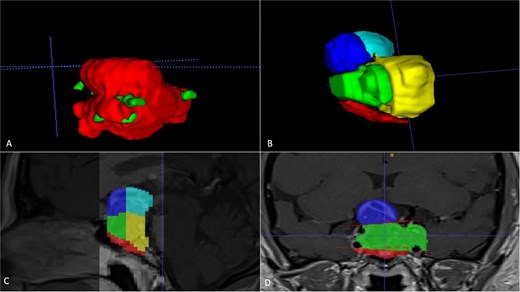

A 42-year-old patient who suddenly presented with headache and visual disturbances. The examination confirmed bitemporal hemianopsia, as well as bilateral papilledema. An MRI study obtained the following sequences: T1, T2, and T1 with contrast (Fig. 4). Manual 3D segmentation was performed to observe the intratumoral components and classify the different anatomical portions of the tumor, as well as its total estimated tumor volume and area (Fig. 5 and Table 2). The importance of reconstruction, in this case, lay in knowing the areas that were possibly not going to be so easily accessible through this endoscopic approach, as well as in calculating the volume of the tumor per segment and the possibility of having residual tumors in less accessible segments.

Manual planimetric volumetric segmentation. (A) Calculation of total tumor volume (red) and its relationship with the internal carotid artery (green). (B) Volumetry by zones. (C and D) Areas shown in sagittal and coronal planimetry.

| Geometric volumetry . | 3D volumetry . | Zone 1 Red (Intraspenoidal) . | Zone 2 Green (Intercarotid) . | Zone 3 Blue stronge (Supracarotid suprasellar) . | Zone 4 Yellow (Retrocarotid intraselar) . | Zone 5 Blue clear (Supraselar retrocarotid) . |

|---|---|---|---|---|---|---|

| 16 cubic centimeters | 21 cubic centimeters | 1.7 cubic centimeters | 3.7 cubic centimeters | 2.3 cubic centimeters | 9.7 cubic centimeters | 3.6 cubic centimeters |